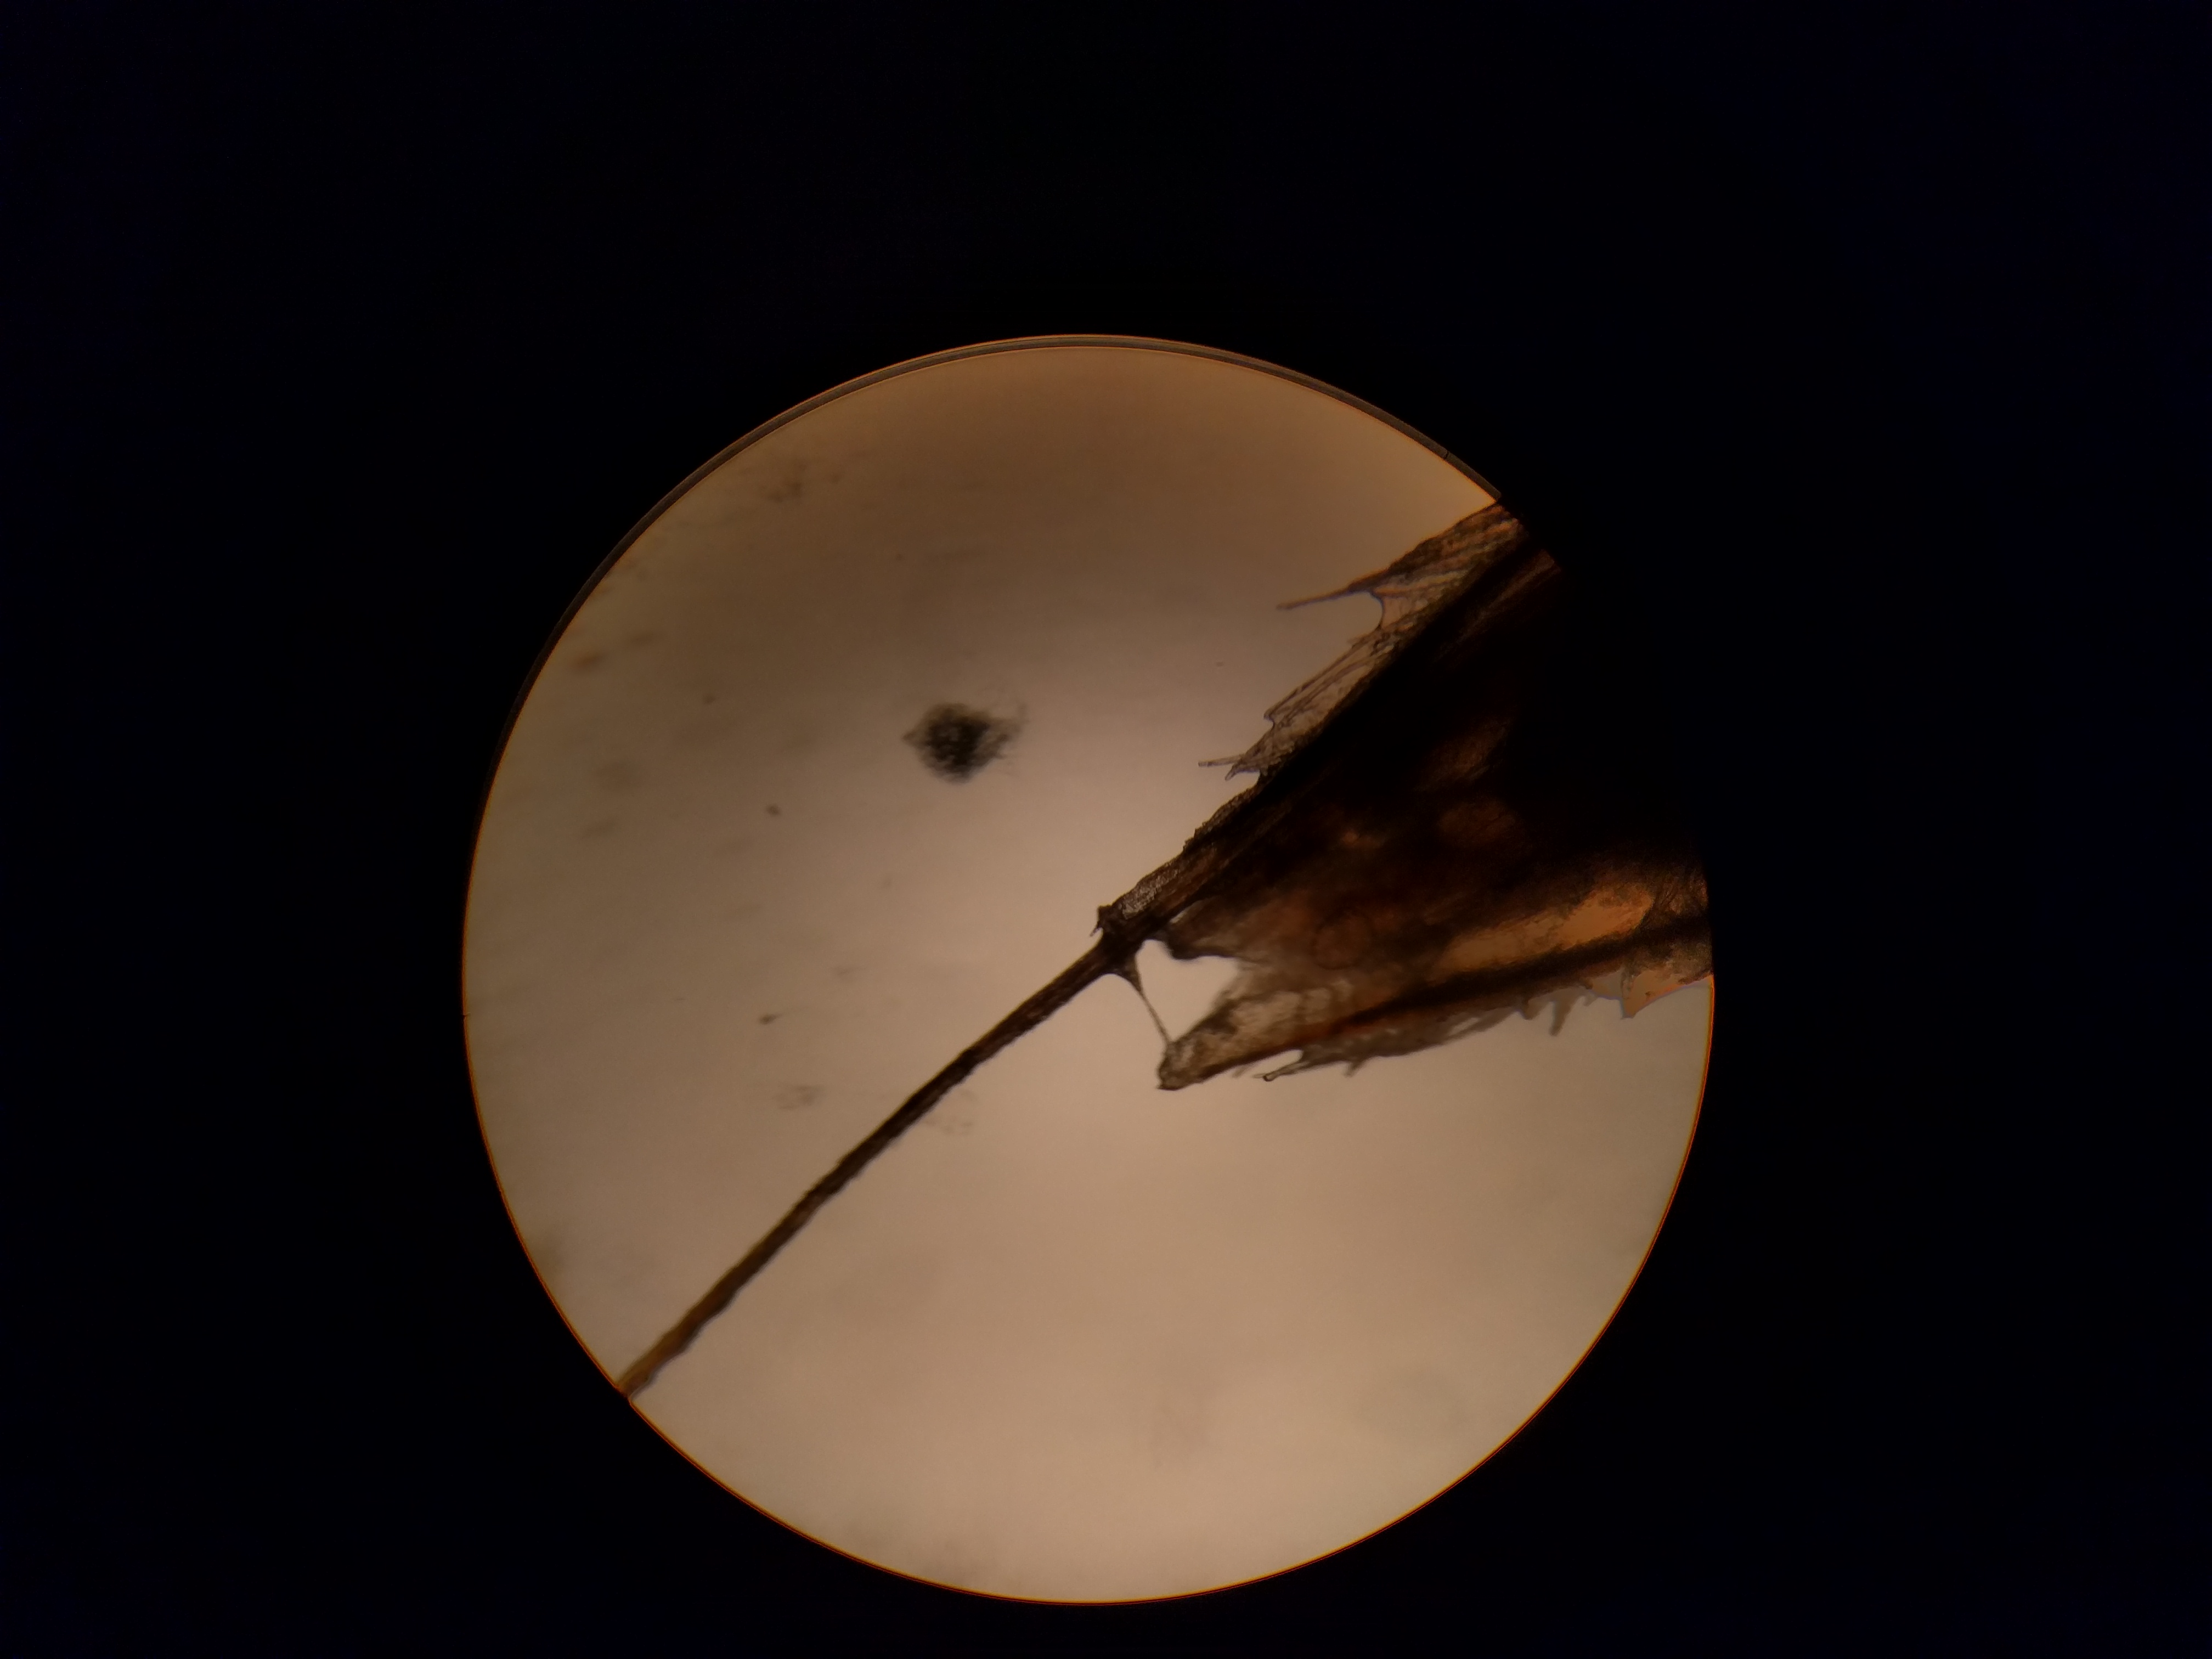

De lastpak onder de microscoop:

aan de linkerkant zit nog een lange venijnige staart (zie hieronder)